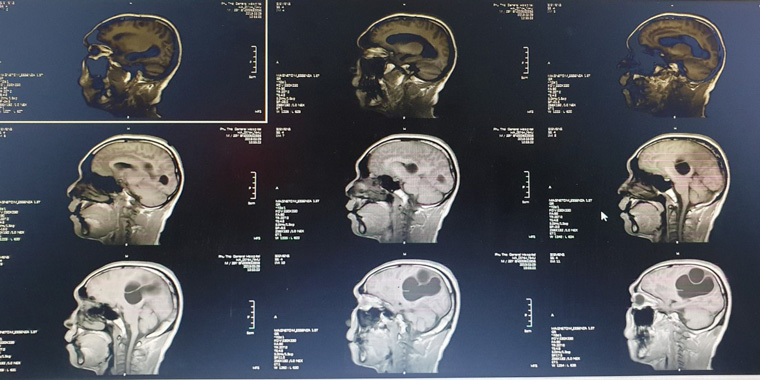

| Hình ảnh tổ sán lớn trong não trên hình ảnh phim chụp |

Sau khi chụp CT, MRI sọ não, bác sĩ phát hiện một ổ sán khổng lồ ở bán cầu não trái và vùng thái dương đỉnh phải. Phù não đè đẩy đường giữa. Bệnh nhân được chỉ định can thiệp ngoại khoa cấp cứu vào lúc 23h ngày 9/3.